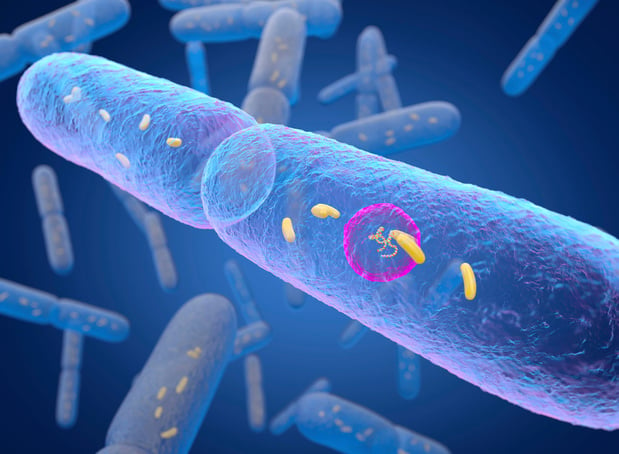

Cancer de la prostate : des bactéries intestinales favoriseraient sa croissance

27/10/2021

Une étude montre que chez les souris castrées et chez les personnes suivant un traitement de privation androgénique, certaines bactéries intestinales communes produisent des androgènes qui sont facilement absorbés dans la circulation sanguine. ces androgènes favoriseraient la croissance du cancer de la prostate et sa résistance à l'hormonothérapie.